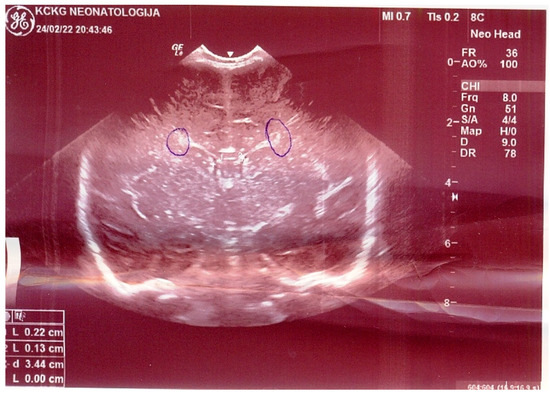

| Clinical picture at admission in Pediatric Clinic UCC | NN1 had a preserved sensorium, was high febrile 39.4 °C (rectal), with tachy-dyspnea, sobs, and moans, indents jugulum, dissatisfied cries, TM 4050 g, subclinical jaundice of the skin, and visible mucosa. Auscultation revealed attenuated respiratory sound, diffusely fine crackles, SaO2 82%, R 56/min, F 196/min. The umbilical stump persisted, the surrounding skin became red and swollen, there was hypotonia of the body axis, large fontanelle within the bony borders, greatness 20 × 30 mm. The other physical findings were normal. | NN2 had the preserved sensorium, was afebrile 37.7 °C (rectal), TM 3920 g, eupnoeic, presented sobs and moans, plethoric and icteric skin, nasal vestibules filled with seromucous secretion, and hyperemic throat. Auscultatory revealed a normal breathing sound is heard with transmitted wheezes from the upper parts of the airways and systolic murmur of 1-2/6 according to Levin, SaO2 97%, R 32/min, F 168/min. The umbilical stump persisted, thin, and the borders developed a serous–hemorrhagic discharge. There was mild hypotonia of the shoulder girdle and trunk axis, primitive reflexes were slowly elicited, large fontanelle was below the plane of the bony borders, and slightly spaced sutures, greatness 40 × 40 mm. The other physical findings were normal. |